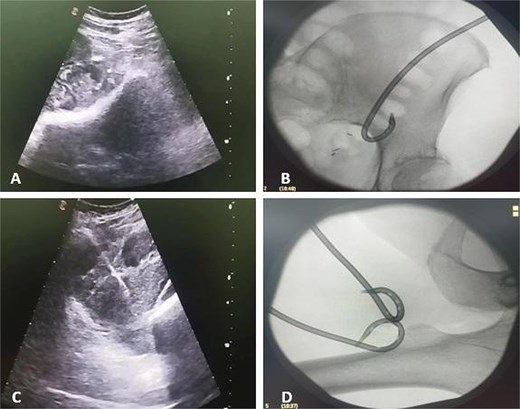

Due to the complex anatomy, a single access was deemed insufficient. Under real-time ultrasound and fluoroscopic guidance, a retroperitoneal approach was first used: an 18-G needle and guidewire were advanced in the left midaxillary line parallel to the iliac crest, followed by tract dilation and placement of a 12-G pigtail catheter into the psoas component. Subsequently, two additional 12G catheters were placed percutaneously via a femoral approach into the thigh extension (Fig. 2). In total, ~200 ml of purulent material was drained. The localization of the drains was confirmed by subsequent CT (Fig. 3).

Ultrasound and fluoroscopy show multi-access percutaneous drainage with one retroperitoneal and two femoral catheters. (A) Ultrasound-guided retroperitoneal puncture into the psoas collection. (B) Fluoroscopic image demonstrating catheter placement in the psoas component. (C) Ultrasound-guided puncture of the thigh extension. (D) Fluoroscopic confirmation of one retroperitoneal and two femoral drains in situ.